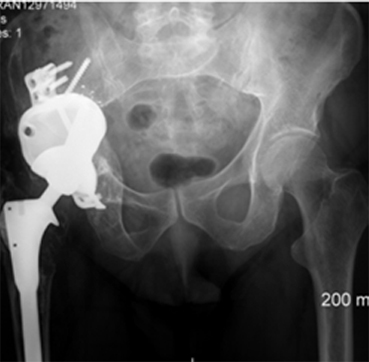

The patient, a 49-year-old woman, underwent metal-on-metal (MoM) hip resurfacing procedure in 2001 due to a unilateral hip dysplasia (DDH). 17 years later, she presented with mild hip pain but extensive loss of bone in the pelvis which was presumably caused by an inflammatory reaction to metal wear debris. Her blood metal ion levels were 100 times higher (cobalt 188 bbp and chromium 126 bbp) than from patients with well-functioning MoM hips.

The case posed multiple challenges. The patient was at imminent risk of pelvic fracture without surgery. However, surgery itself also risked fracture of the pelvis during implant removal. Furthermore, the remaining pelvic bone was poisoned by metal debris and thus the patient’s bone integrity was compromised, which could affect the stability of a new implant.

A multidisciplinary team decided that revision surgery was necessary due to the risk of fracture and very high metal ion levels. The plan involved removing the existing MoM implant and fitting a custom 3D-printed acetabular cup. The procedure required meticulous care to avoid causing fractures during implant removal. The new cup would only be effective if the pelvis remained intact.

The operation was successful, with minimal bone loss during implant removal. A custom-made titanium acetabular cup was fitted and stabilized with screws. Postoperative imaging confirmed correct implant positioning and satisfactory fixation. The patient’s recovery was positive, with significant reductions in metal ion levels and the restoration of pain-free hip function.

This case represents ALTR with MoM, which was characterized by extensive osteolysis of pelvic bone, which was presumably caused by metal wear debris. Elevated blood levels of chromium and cobalt further supported this hypothesis.

This case demonstrates the importance of precise surgical planning and execution in complex hip revision surgeries. The use of 3D-printed implants tailored to the patient's anatomy greatly improved the chances of successful fixation despite significant bone loss. Update at 6 years post operative is that the patient living a full and active life with excellent hip function. More details about this type of surgery has been published by Professor Hart: